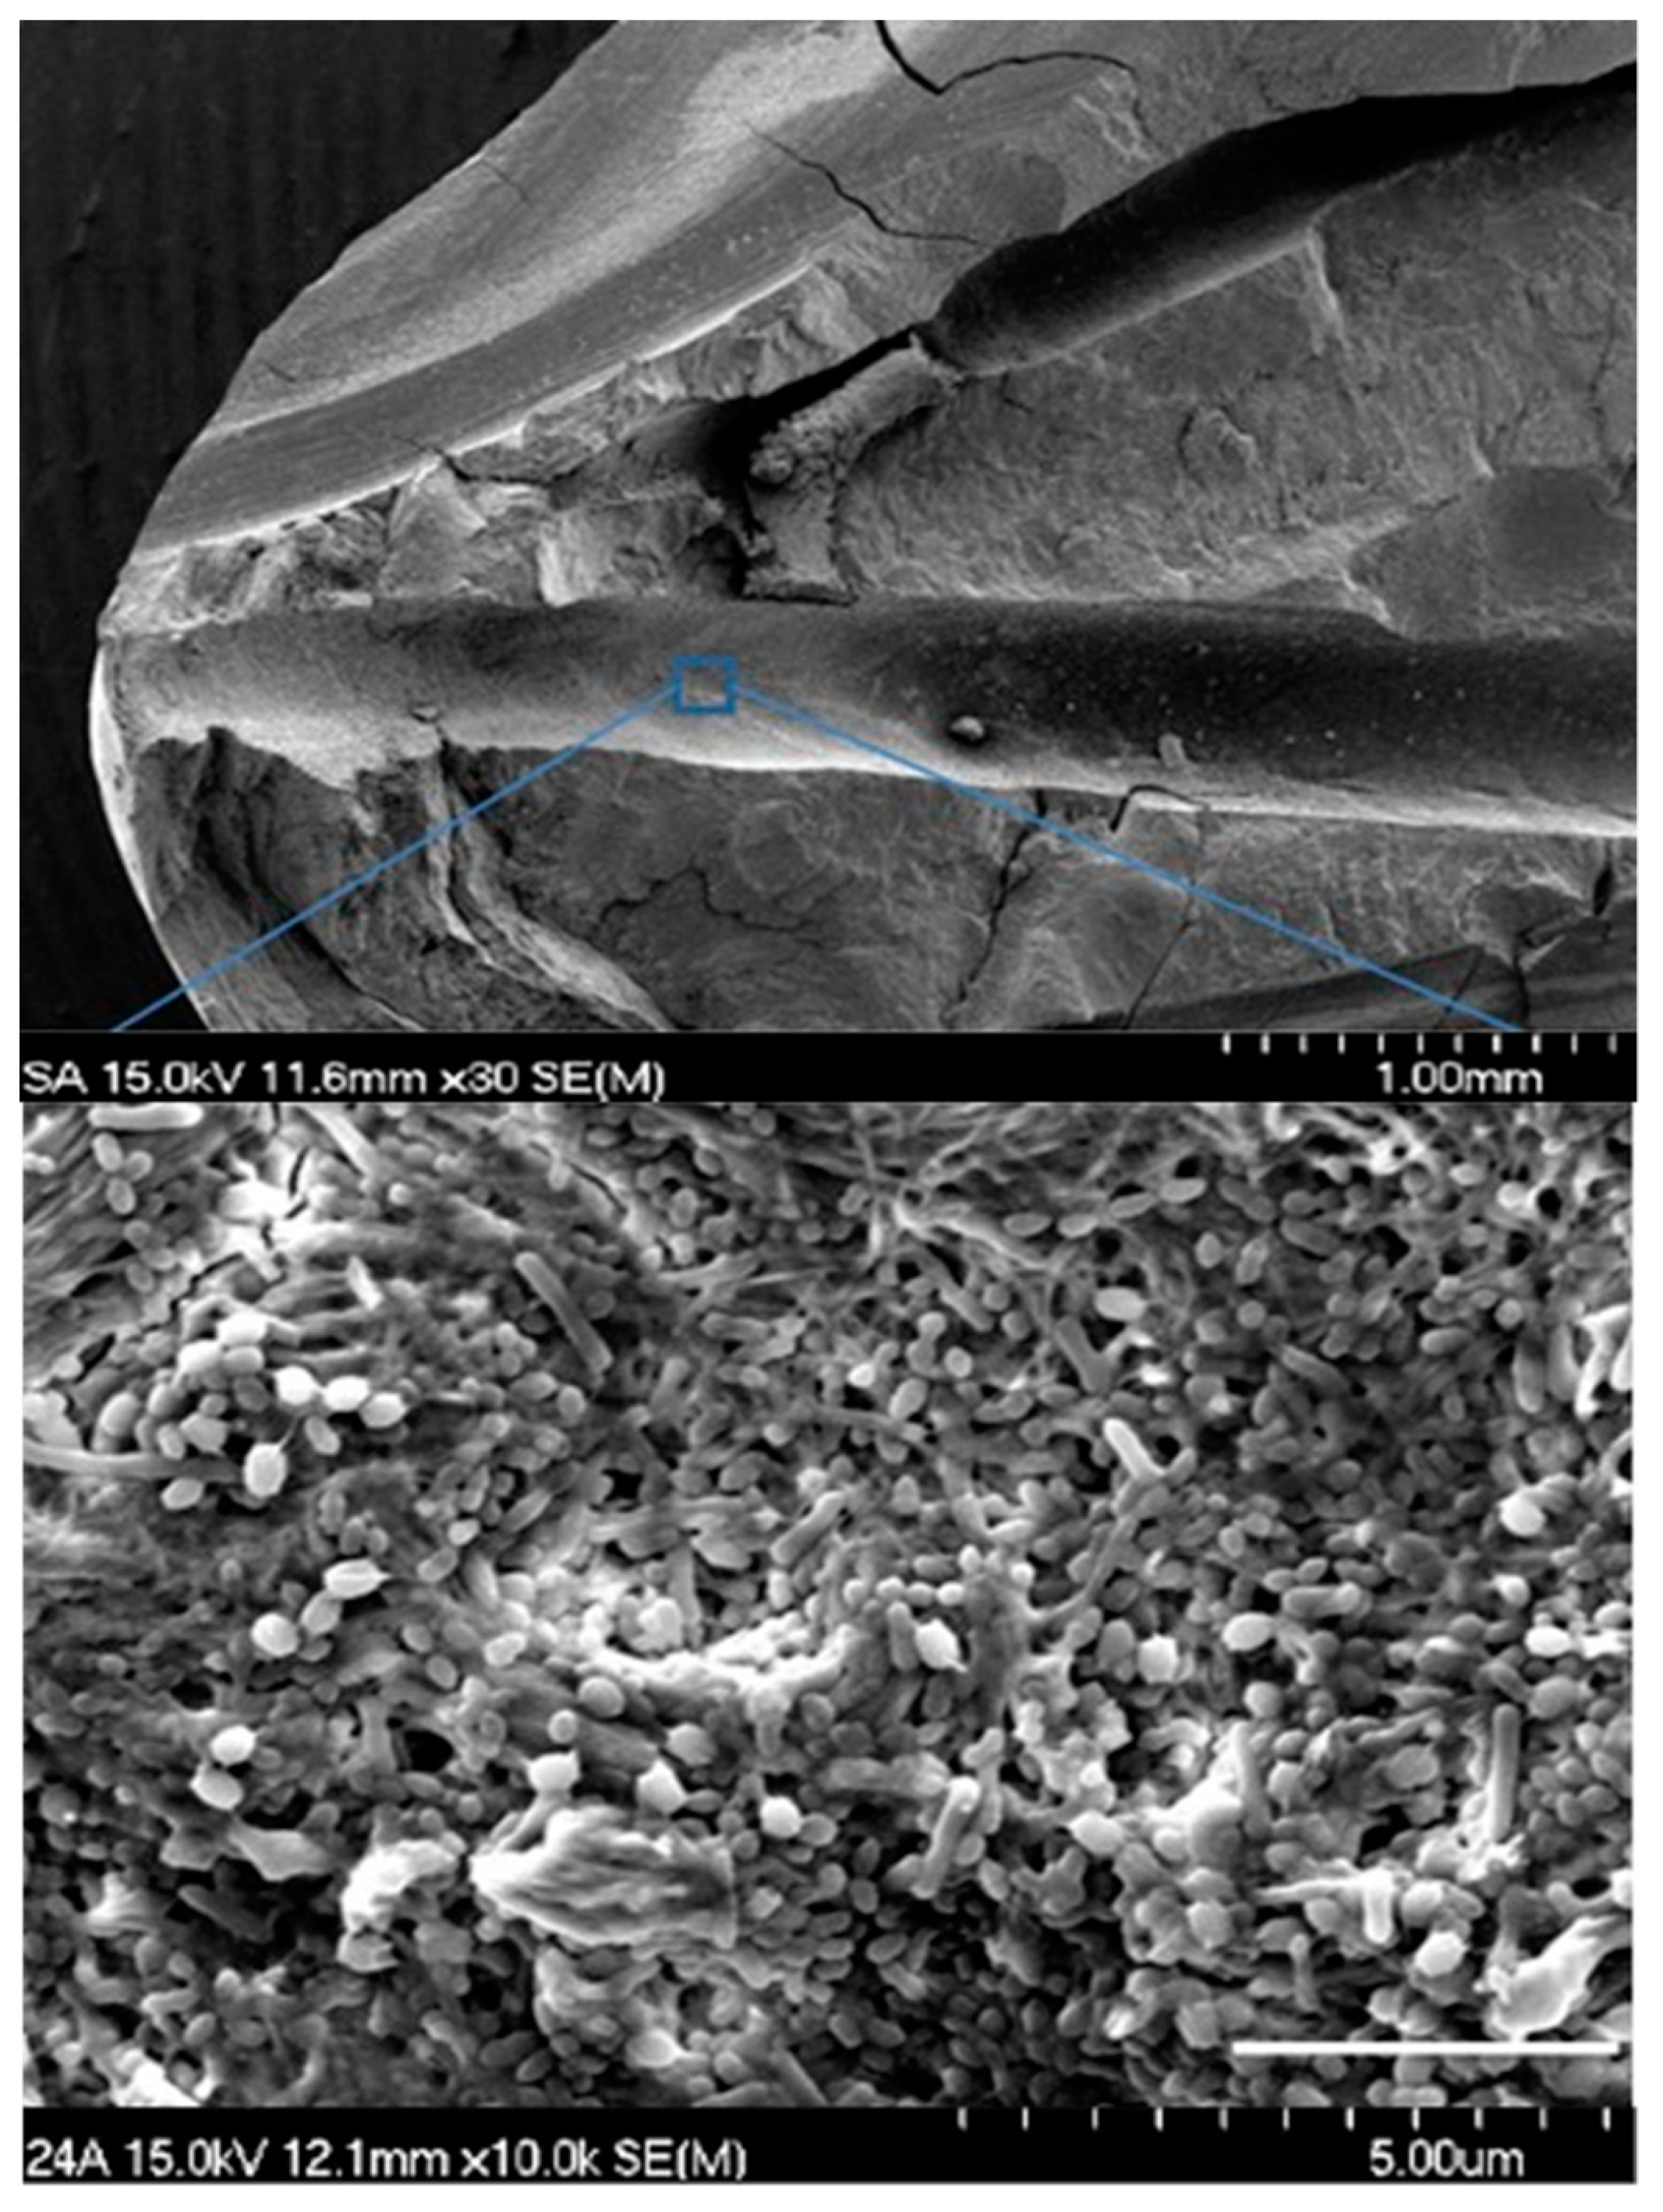

2.4. Confirmation of Infection

2.6. Sample Processing